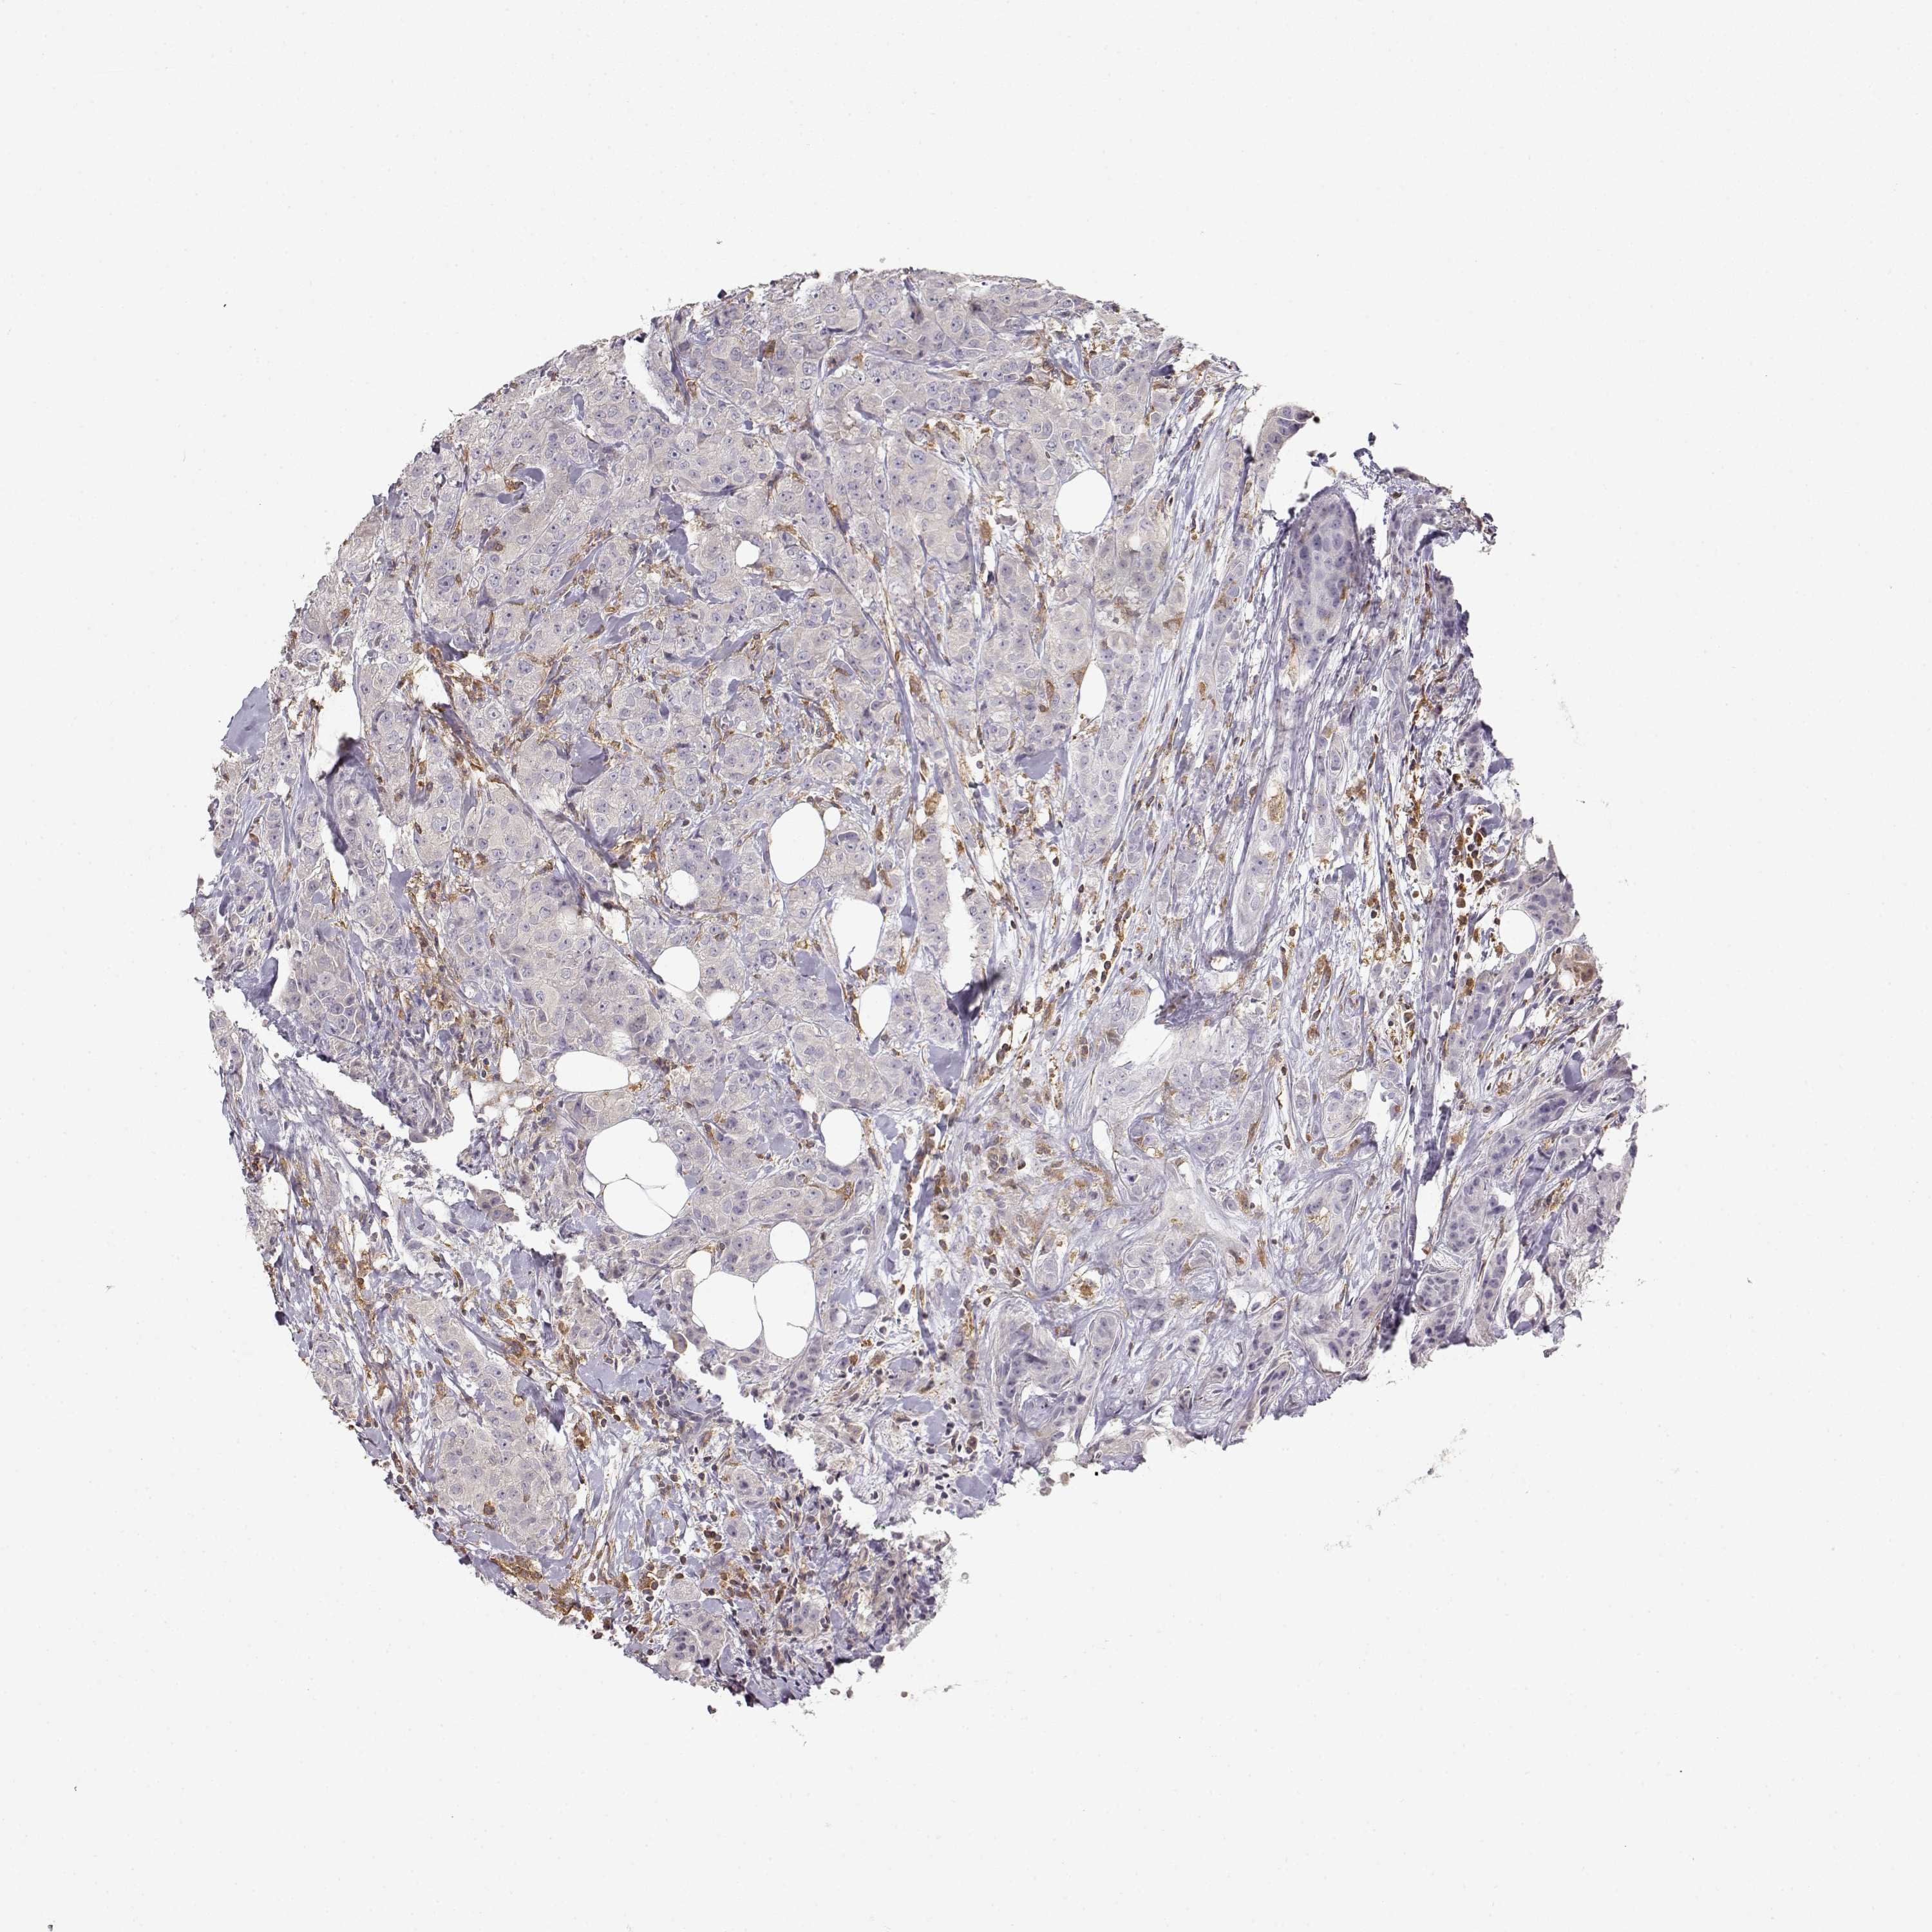

CANCER BREAST CANCER Show tissue menu

BRCA TCGA BRCA VALIDATION PROTEIN EXPRESSION

Breast cancer

Human cancer